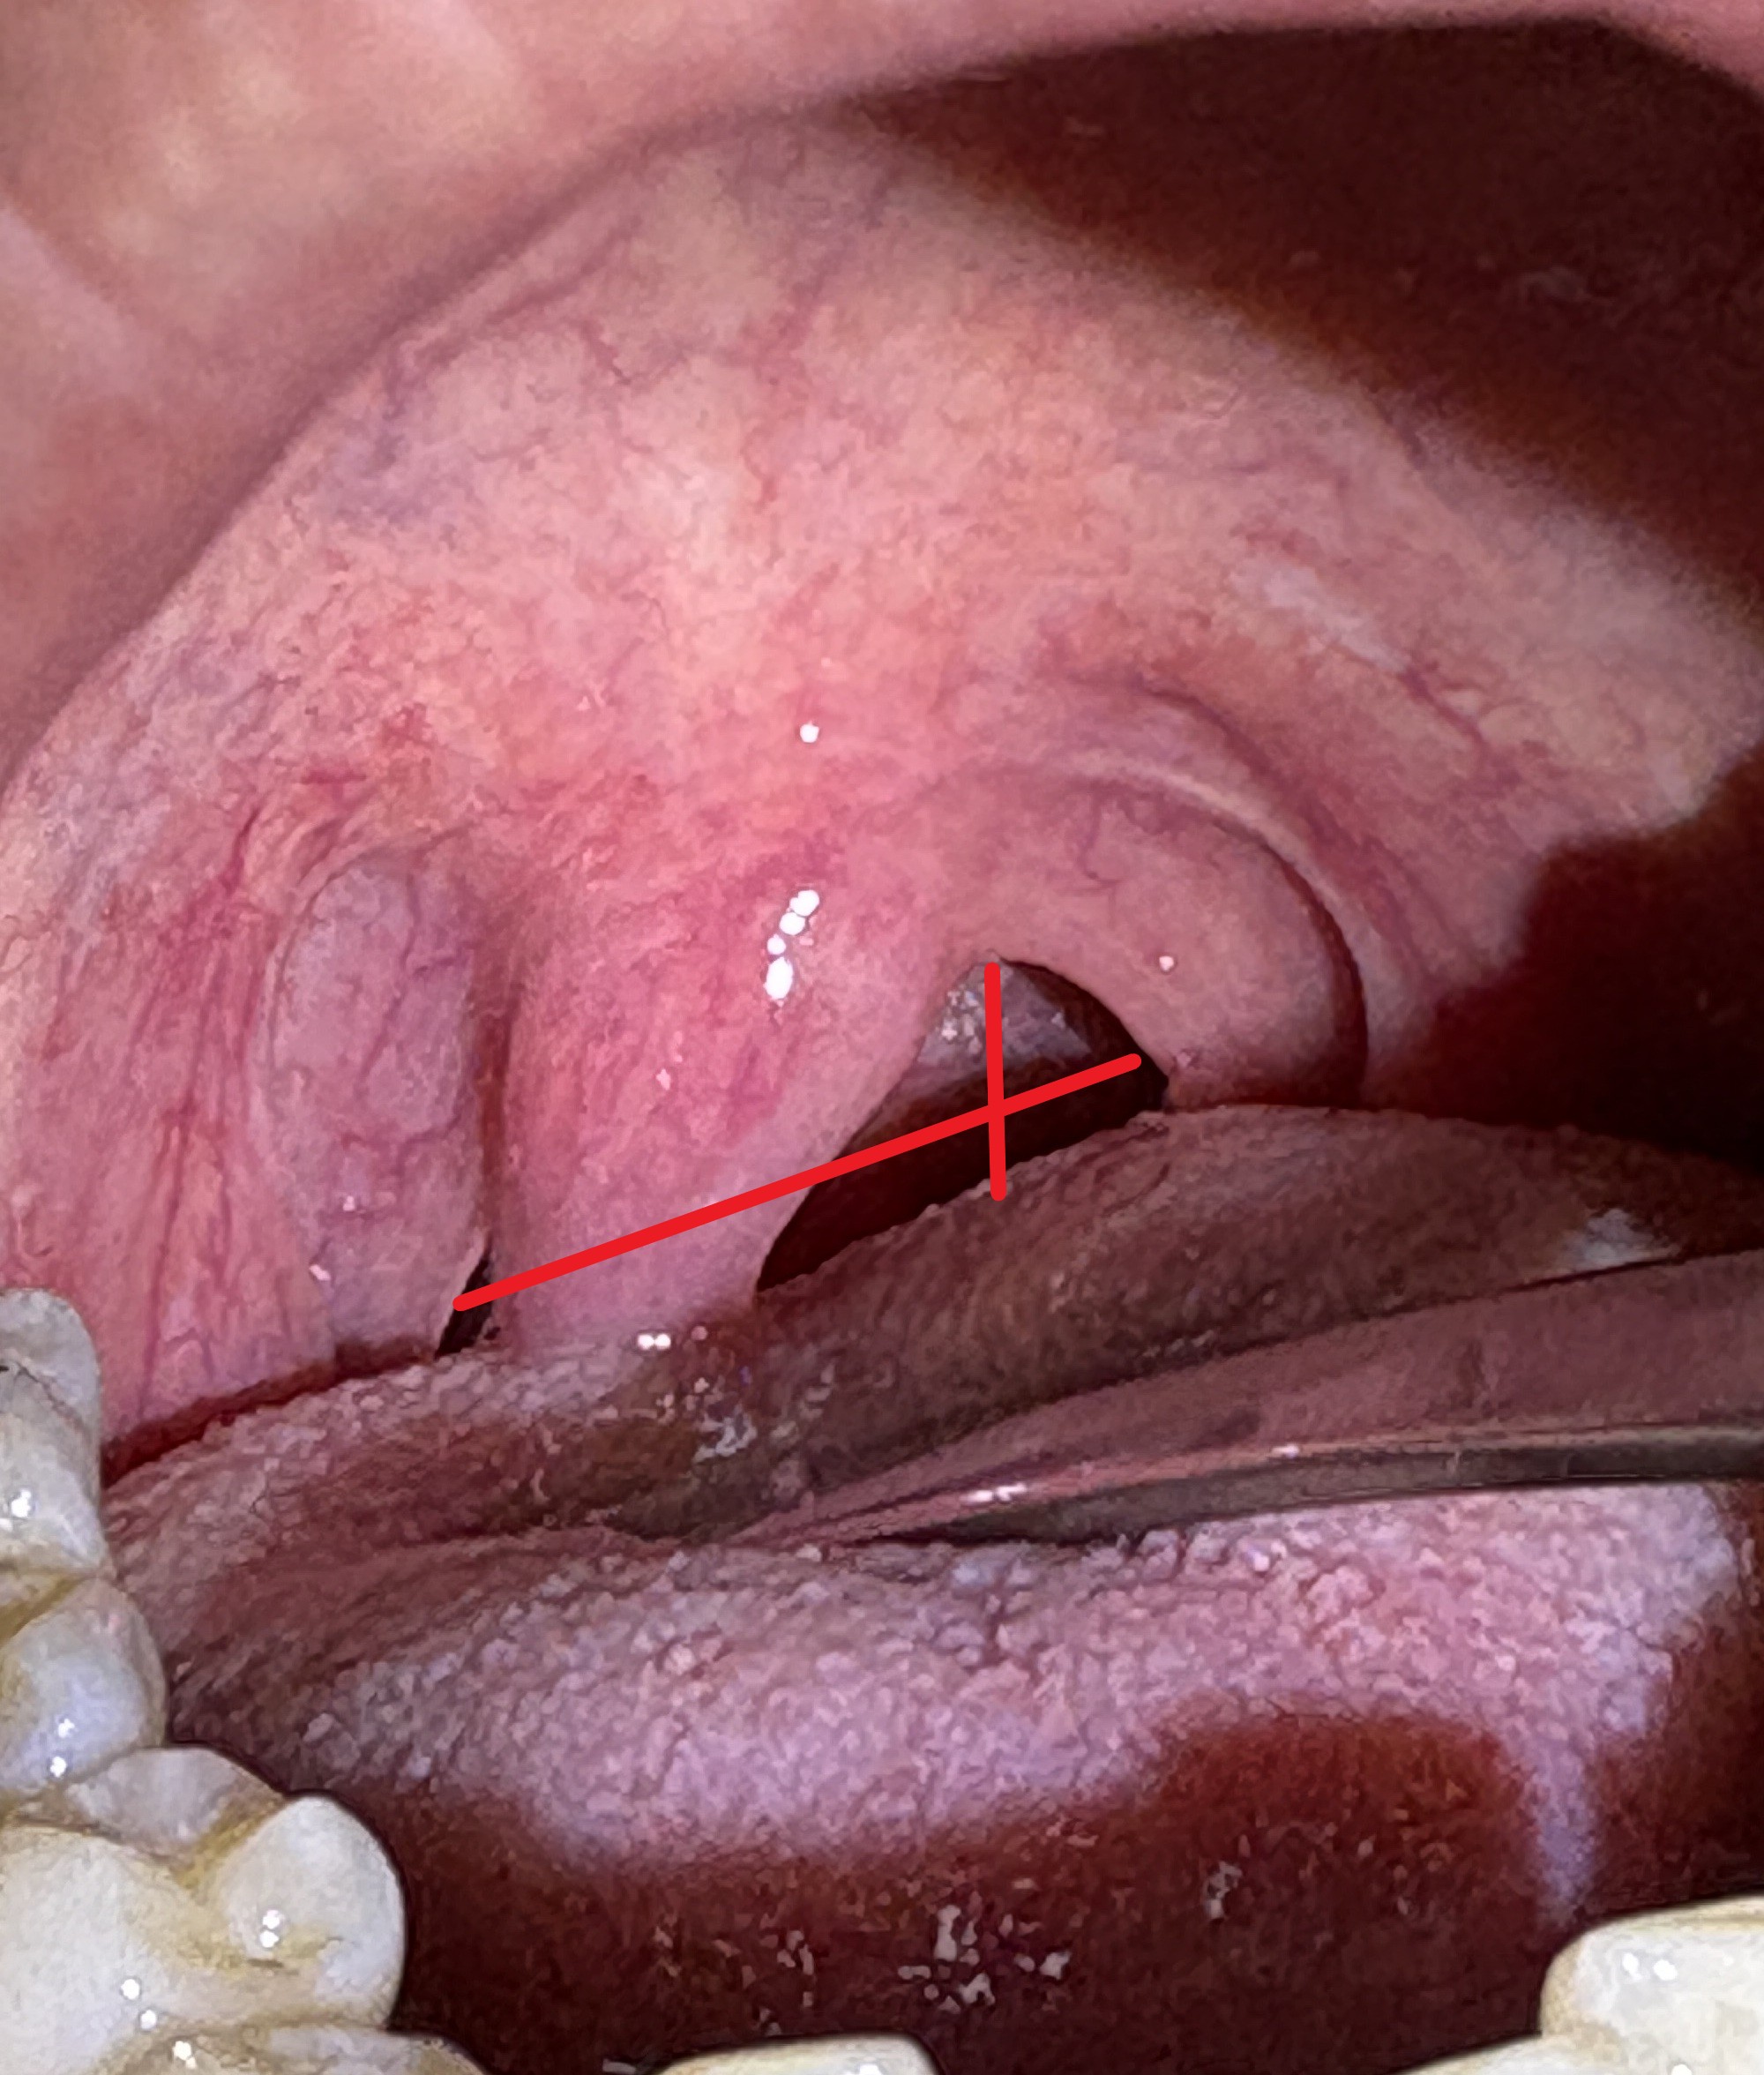

喉が上下・左右に狭い

IMG_0985 - コピー - コピー